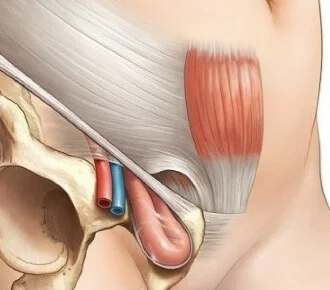

- Hernioplastias de Pared abdominal